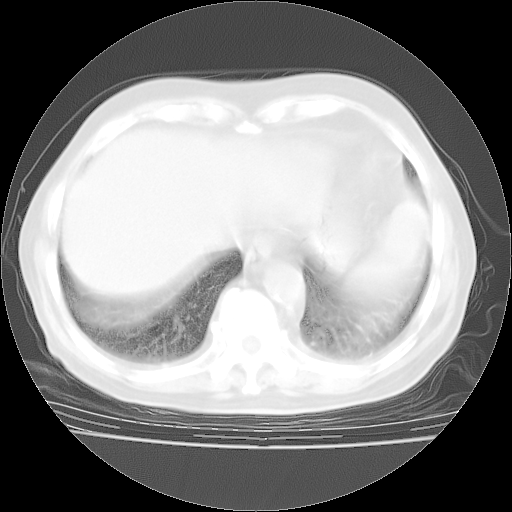

4月28日肺部CT——再次出现类似去年5月9日——透光度降低,“间质性”改变。

个人阅读4.14日肺部CT平扫:纵隔窗无异常,但肺窗示:双下肺内、后基底段有片絮状侵润影,部位以后基底段为著,以间质改变为主,呈急性肺泡炎征像,和首次住院影像学有相似之处。仅是个人读片,明日请相关专家再读片哈。其它建议同上。

今请临免主任会诊后认为:4月14日胸部CT已有双下肺间质性改变。患者病情复发多系激素减量过快不正规所致。目前甲强龙80mg/日,一周后酌情开始减量,不易过快。环磷酰胺若已停用,暂不使用。他同意目前抗菌药物使用,但应考虑是否加用B-内酰胺类抗菌药物(中性细胞明显增高);2、结核复发目前依据不足;3、若免疫全套各项指标正常,考虑多系特发性肺间质炎可能大。4、加强支持,并注意保护胃黏膜。